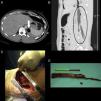

Varón de 27 años, que tras caída accidental sobre rama de árbol, sufrió empalamiento tóraco-abdominal con punto de entrada en región infraclavicular izquierda. Se realizó TAC tóraco-abdominal (fig. 1A y B) que mostró enfisema subcutáneo en pared torácica, importante neumotórax izquierdo con colapso pulmonar, lesiones parenquimatosas en ambos lóbulos pulmonares y presencia de cuerpo extraño de densidad aire de 2cm de grosor que se extendía craneocaudalmente desde el pilar izquierdo del diafragma hasta el músculo psoas y músculo paravertebral posterior izquierdo con 2 extremos distales que terminaban a la altura de la cresta ilíaca izquierda.

TAC tóraco-abdominal (A-B) en el que se visualiza fragmento de madera de 20cm de longitud por 2cm de grosor con 2 extremos distales (morfología de Y invertida) que se extiende craneocaudalmente desde el pilar izquierdo del diafragma hasta el músculo psoas y musculatura paravertebral izquierda. Imágenes del campo quirúrgico en el que se aprecia la rama de árbol en la cavidad torácica (C) y del cuerpo extraño (D) una vez extraído bajo visión directa.

Se llevó a cabo cirugía urgente, realizándose toracotomía y lumbotomía izquierdas. Los hallazgos quirúrgicos (fig. 1C y D) incluyeron: hemotórax, laceraciones de ambos lóbulos pulmonares, sin lesión vascular ni bronquial y rama de árbol de 20×2cm con morfología de Y invertida incrustada en diafragma y músculo psoas, en localización retroperitoneal y presencia de restos vegetales en cavidad pleural.